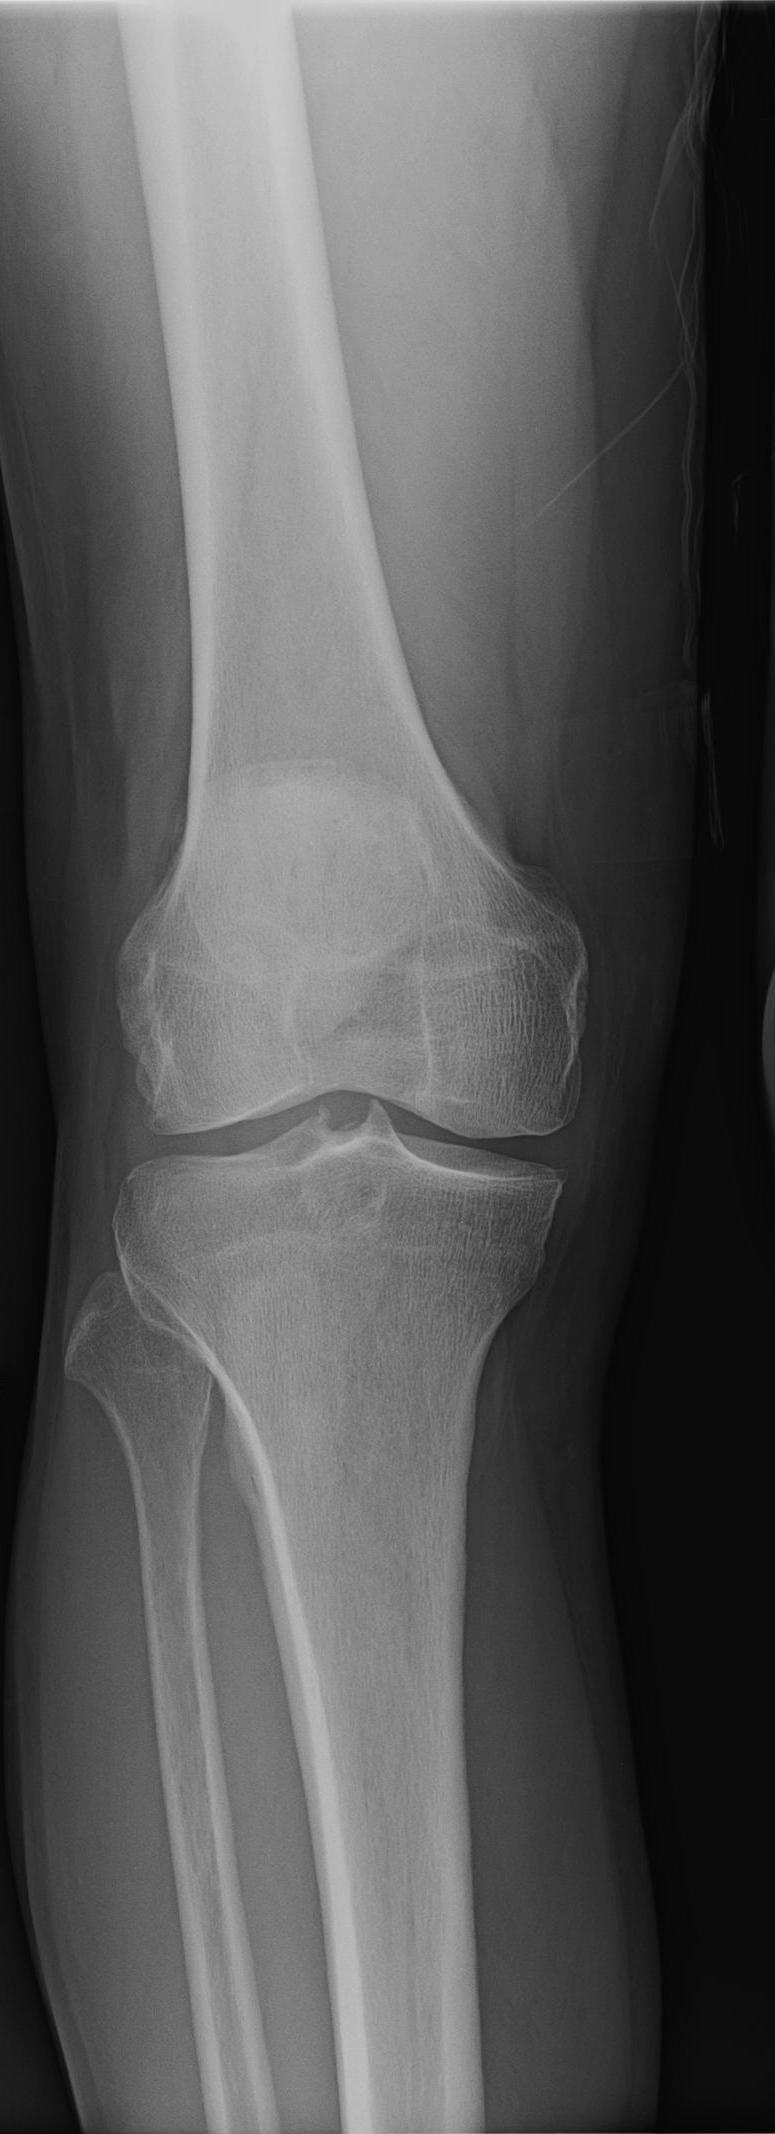

Xray Knee Osteoarthritis Case Study Knee Osteoarthritis The study shows a grade 3 osteoarthritis that is accompanied by. Osteoarthritis (oa) is a prevalent condition in india. To investigate risk factors related to the knee osteoarthritis a case. The blockbuster drug semaglutide, sold as ozempic for diabetes and as wegovy for. The symptoms and signs of knee osteoarthritis include pain, stiffness, reduced joint motion, and muscle weakness. The. Case Study Knee Osteoarthritis.

Osteoarthritis of the knee Image Case Study Knee Osteoarthritis Knee osteoarthritis (oa) causes reduced mobility, i.e., gait walking. Osteoarthritis (oa) is a prevalent condition in india. The blockbuster drug semaglutide, sold as ozempic for diabetes and as wegovy for. It can cause functional limitations and affect the quality of. Patients who experience discomfort or joint instability. The symptoms and signs of knee osteoarthritis include pain, stiffness, reduced joint motion,. Case Study Knee Osteoarthritis.